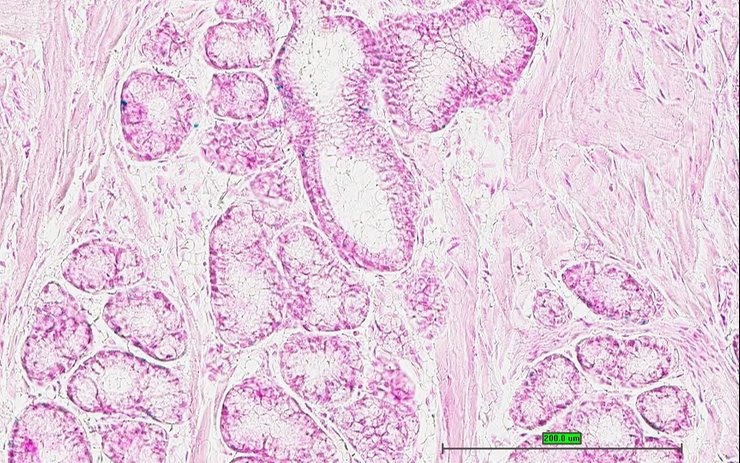

TS28: prostate gland Present UC Davis_1871164

Specimen UC Davis_1871165: postnatal adult; Epha6tm1b(KOMP)Wtsi/Epha6+ (more )